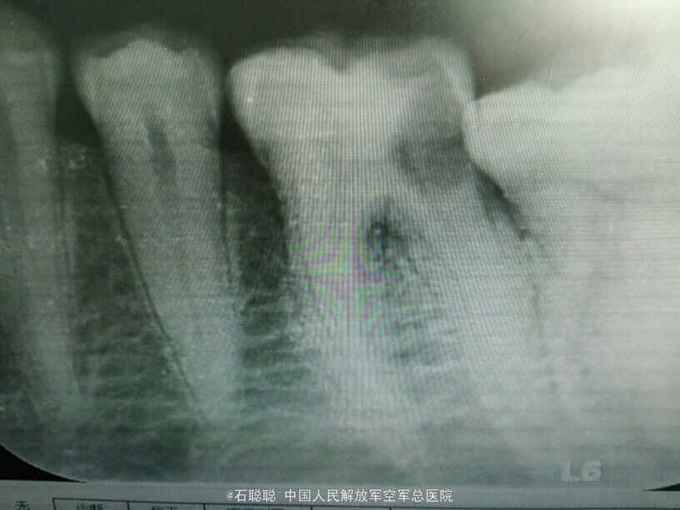

检查:左下6合面远中大面积龋洞,腐质量中等,腐质软,探+,冷++,叩诊不适,不松动,牙龈未见异常 根尖片:左下6牙冠远中低密度影像,及髓,牙周膜及根尖未见异常